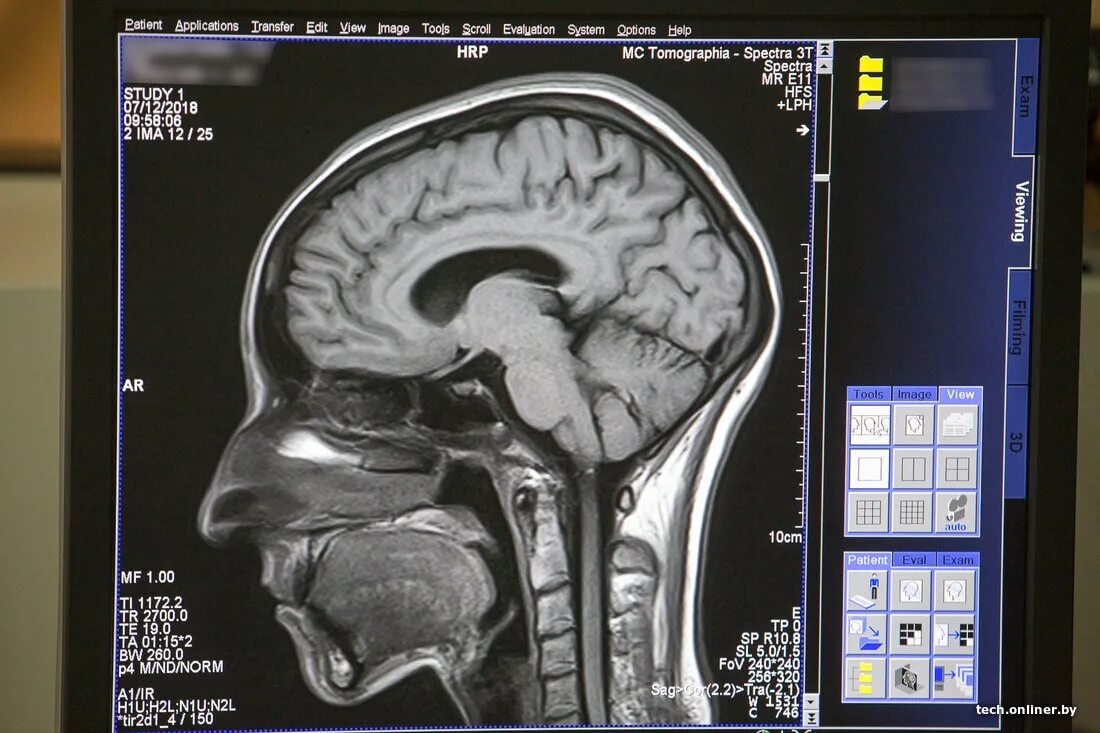

Данные мрт